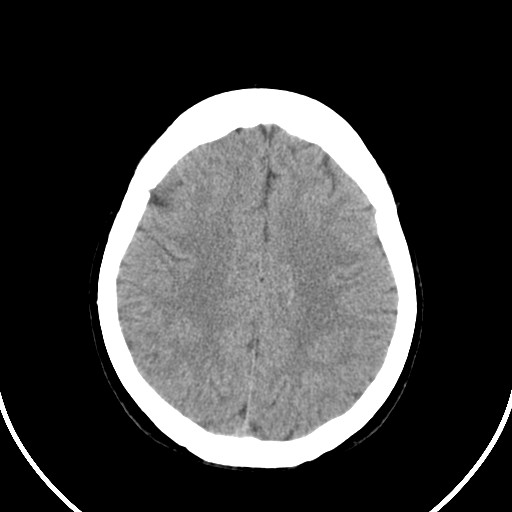

女,56岁,右中指淤肿,右手麻痹1天

右侧侧脑室旁脑白质腔隙性脑梗死。

右侧基底节多发小梗塞

作者: huangyinshan    时间: 2009-8-25 15:37

右基底结区腔梗

右侧基底节区腔隙性脑梗塞

右侧基底节多发腔梗!

双侧侧脑室额角旁对称性略低密度影,边缘模糊,无占位效应,考虑轻度脑白质稀疏症(病人有高血压吗).,右枕叶低密度影多为伪影,不放心薄扫一下.

考虑脑白质病。

考虑脑白质病

右枕叶条状低密度影不应该忽略可能极具意义